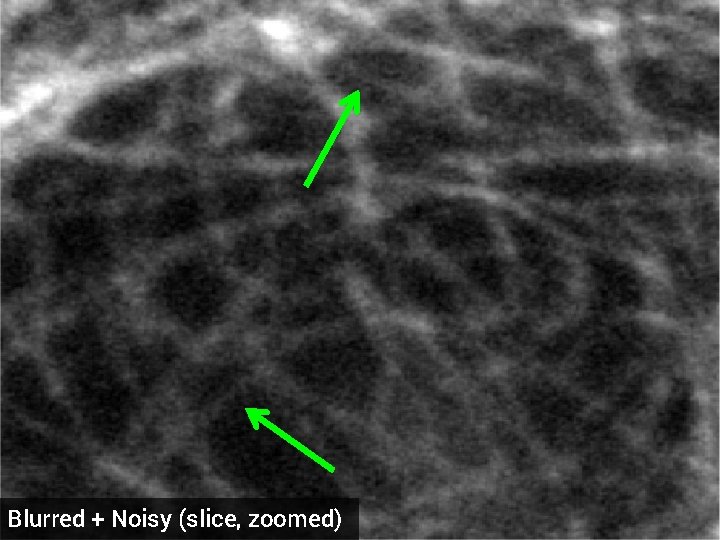

Deblurring of 3 -D Florescence Microscopy § 1024 x 17 voxels § 3 x 3 x 3 Gaussian blur kernel, std. dev = 0. 05 § 5 d. B additive Gaussian noise § Optimized regularization parameter original dataset (z-slice)

Blurred + Noisy (slice, zoomed)

TV deblurred (slice, zoomed) SNR = 14. 50 d. B

HDTV 3 deblurred (slice, zoomed) SNR = 15. 23 d. B